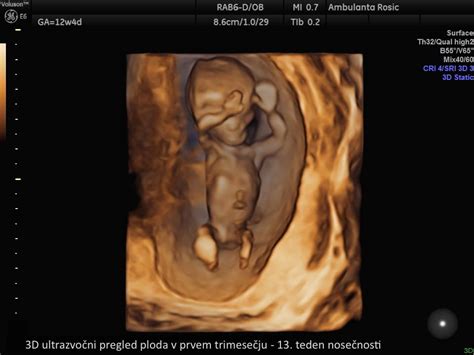

Ultrazvočni Pregled Nuhalne Svetline in Zgodnje Anatomije Ploda

Ta ultrazvočni pregled se izvede med 11. in 14. tednom nosečnosti. Med njim se podrobno pregleda celoten plod, vključno z glavo, obrazom, okončinami, trebušno steno, hrbtenico, posteljico, popkovnico in plodovnico. Izmeri se nuhalna svetlina (debelina kožnega nabora na vratu ploda), ki je pomemben marker za kromosomske nepravilnosti.